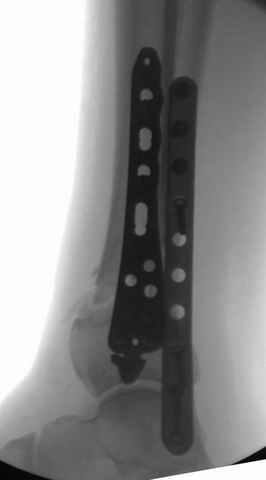

На снимках варианты фиксации малоберцовой:

№ 6-11 при pilon percutaneus fixation